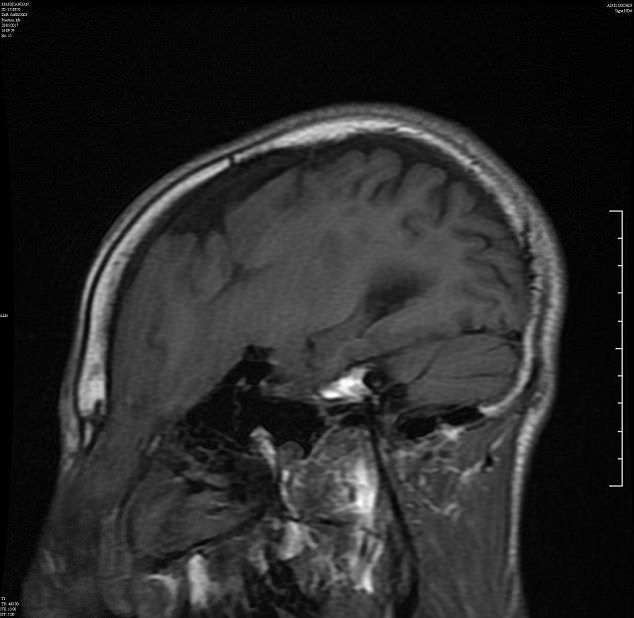

gif_animation インドにて、学校で「顔面に性器が付いてるようだ」といじめられてる13歳の少年の顔。”頭蓋脳ヘルニア” という病気により鼻上が飛び出し、下に垂れ下がっている。レントゲン画像+11時間にも及ぶ手術の結果、無事腫瘍を取り除いた少年の画像。